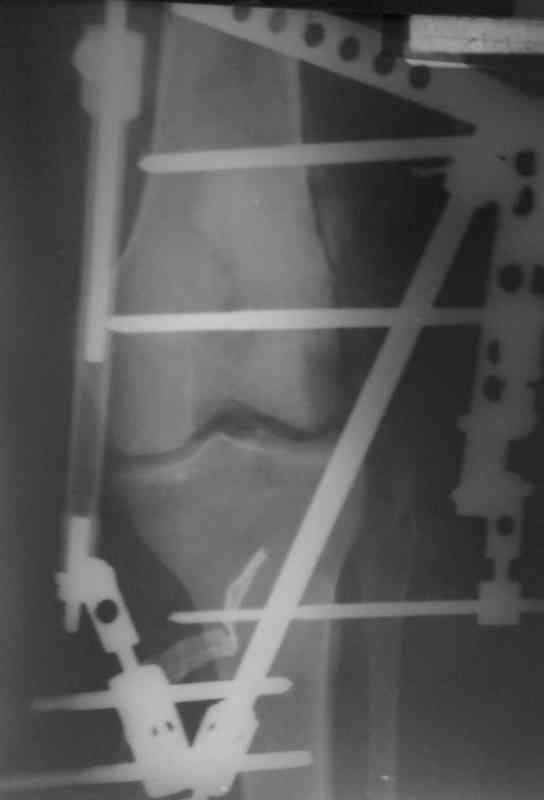

Bolnoi 27 let, DTP, Motorcycle trauma, postupil v kreane tiajelom sostoianii, osnovnia trauma- otkrity totalny vivih levogo kolennogo sustava s povrezdeniem malogo bersovogo nerva, tracionnoi povrezdenia podkolennoi arterii bez narushenia selostnost' sosuda, pomosh' okazanno v nujnum obmeme, kakoe ze mnenie uvazaemih kolleg naschet dalneshego vvedenia bolnogo? Castro

Uvajaemiy kollega! *Pomosh okazano v nujnom ob`eme*- kak ponyat? Vosstanovili krestoobraznih i bokovih svyazok? ili prosto vivih vpravili i fiksirovali AVF. sudya po R-snimkam nadkolennik nahoditsya visoko- znachit povrejdena i sobstvennaya svyazka, kotoraya ne ushita. Potom mojno sostavit plan lecheniya. S uvajeniem Abdurashid.

На ренгенограмме хорошая аппозиция костей коленного сустава, но надколенник находится подозрительно высоко, поэтому необходимо убедиться в отсутствии повреждения связки надколенника.

Аппарат внешней фиксации удаляется в 6-7 недель,

предпочтительно под общим обезболиванием, во время

удаления проверяется стабильность и амплитуда движения в коленном суставе с редрессацией.

При пользовании стержневых наружных фиксаторов,

надо придерживаться правила проведения стержней подальше от зоны, на бедре лучше накладывать стержни косо передне-латерально, между брюшками прямой и vastus lateralis, а на голени по передне-медиальной поверхности большеберцовой кости, где отсутствует мышцы, иначе

восстановление движения в суставе тяжелее из-за

прошитых мышц спицами или стержнями аппарата.